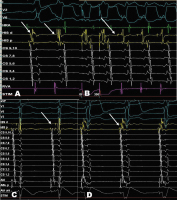

Abbildung 2: Elektrophysiologische Untersuchung mit HRA-, His-, CS- und RVA-Kathetern. (A): Im Sinusrhythmus zeigt sich ein deutliches Fusionspotenzial (Pfeil) im Bereich des distalen His. Auch bei einer spontanen ventrikulären Extrasystole ist die früheste atriale Erregung im Fusionspotenzial an der distalen His-Elektrode. (B): Unter programmierter ventrikulärer Stimulation mit 300 ms kann eine orthodrome AV-Reentrytachykardie mit einer Zykluslänge von 330 ms ausgelöst werden (Pfeil). Früheste retrograde atriale Signale befinden sich am distalen His-Kanal. (C): Nach mechanischer Irritation der His-Region durch den Ablationskatheter ist die Bahn refraktär und ein klassisches His-Signal (Pfeil) kann abgeleitet werden. (D): Schon nach wenigen Minuten erholt sich aber die Bahnleitung erneut (Pfeil). Das His-Signal ist nun wieder im Ventrikelsignal verborgen.